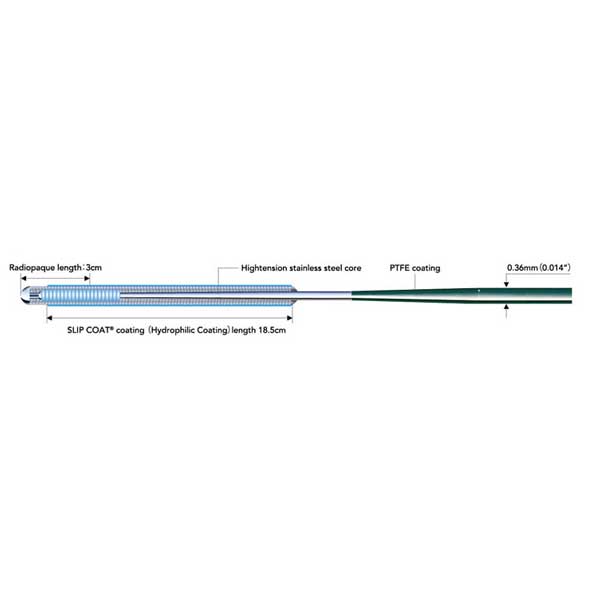

Cruiser / Teleflex (BIOTRONIK Vascular Intervenion)

Coronary Guide Wire Indicated for PTCA applications